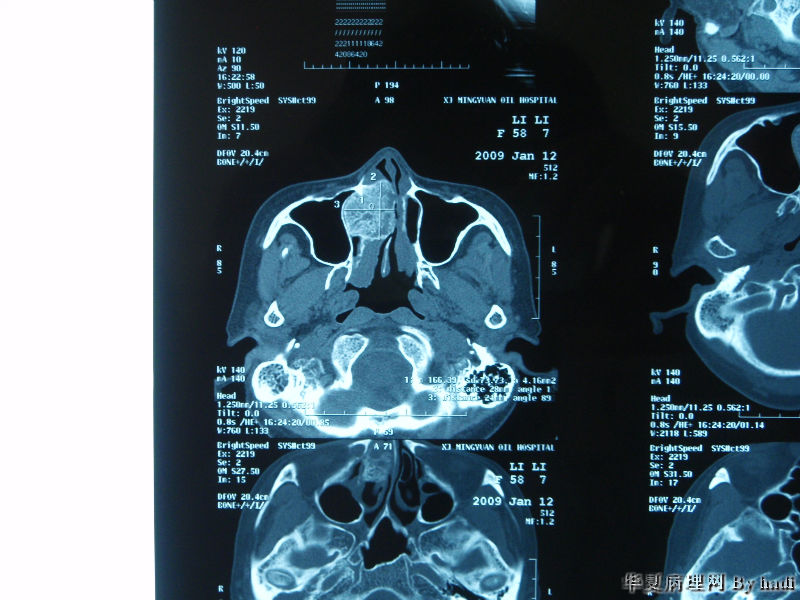

鼻腔肿瘤,成人男性

• 鼻腔肿瘤图1

图1